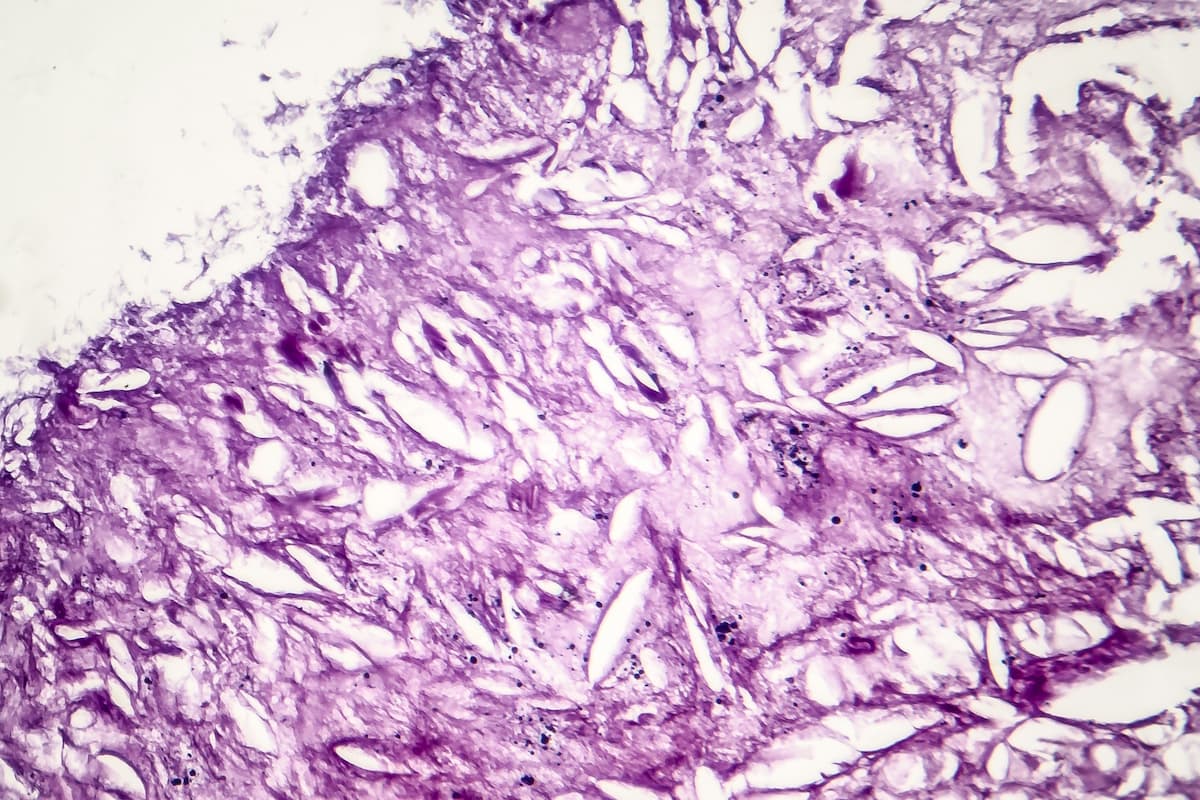

Nemvaleukin is an engineered interleukin-2 (IL-2) variant immunotherapy that was previously granted for orphan drug designation for mucosal melanoma.2 Additionally, enrollment has begun for the global phase 2 ARTISTRY-6 (NCT04830124) trial, which will investigate the anti-tumor activity, safety, and tolerability of nemvaleukin alfa in patients with mucosal melanoma that have previously undergone treatment with anti-PD-L1 therapy.

"We are committed to advancing this important research in mucosal melanoma, a rare and aggressive form of melanoma for which there are very limited treatment options, particularly for those patients previously treated with checkpoint inhibitors,” Hopkinson said.